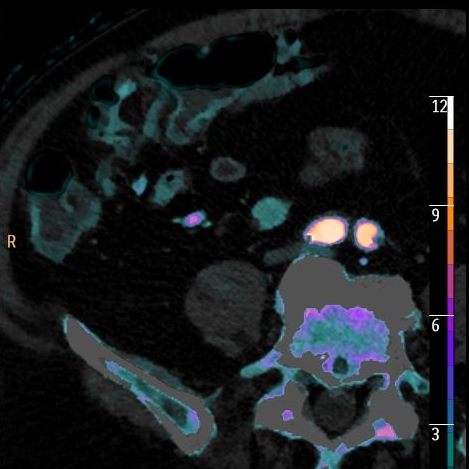

Iodine map shows clear iodine uptake, consistent with tumor.

Iodine overlay nicely depicts the finding